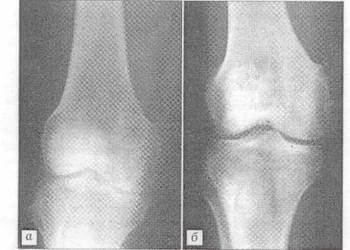

Использование материала Остеоматрикс при импрессионном оскольчатом переломе наружного мыщелка большеберцовой кости по типу Schatzker II